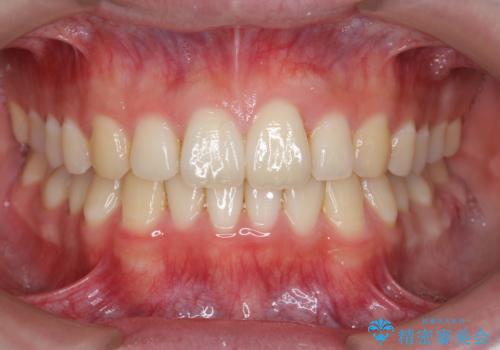

前歯のがたつき・すれちがい咬合を非抜歯で。流行の、格安マウスピースでは難しい、ワンランク上の治療

左下の奥歯を後ろに移動して、中に入ってすれちがっていた小臼歯を並べました。

巷(ちまた)で大きく宣伝している某 格安マウスピース矯正では、奥歯を後ろに動かすことはできないです。

他院で歯を抜かずにマウスピースで難しいといわれた方、ぜひご相談ください。